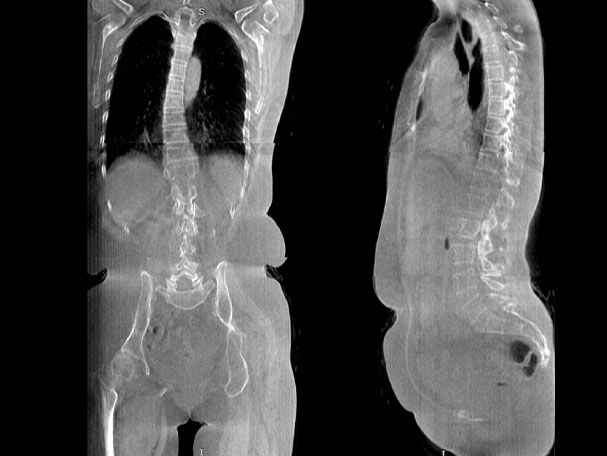

• 全身姿态评估

WR-3D能提供一种负重位状态下全身的姿态和三维空间任一平面平衡评估,使全脊柱术后评价更客观、真实 。通过各种临床参数包括骨盆、脊柱参数评价骨盆、脊柱平衡,避免由于髋膝屈曲造成的代偿性脊柱失衡的发生,WR-3D提供了三维空间任一平面平衡评估测量方法,可以更加定量地评估手术效果 。

VR体绘制重建

气道三维影像重建

FOV最大350mm

支持双腿或双侧髋关节扫描 | 方便对比,降低漏诊误诊